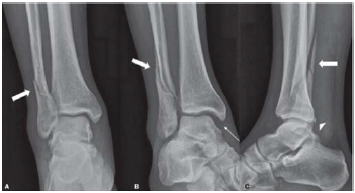

Um paciente de 45 anos de idade sofreu entorse do tornozelo direito durante prática de skate. No hospital, foram realizadas as radiografias representadas na figura.